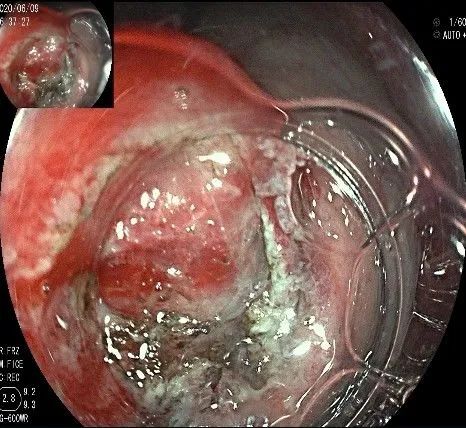

再次进镜观察,齿状线炎性息肉的地方,用圈套器圈套后通电切除。

瘤子切除后,在粘膜切开的地方,固有肌层的纵形肌处形成一个开口。

倒镜观察,隆起已经消失。

夹闭创面的时候做胃镜吸引,利于创面闭合。

创面夹闭完成,反复冲洗观察,无出血及穿孔。结束手术,等待病理结果。